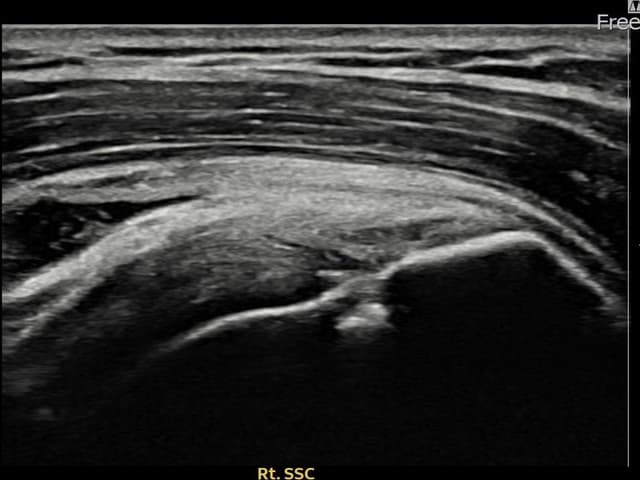

[촬영시기:23.11.28~24.02.06]

[어깨인대 축소봉합술] 우측 어깨 후방 통증과 팔을 바깥으로 돌릴 때 통증이 심해 내원하셨습니다.